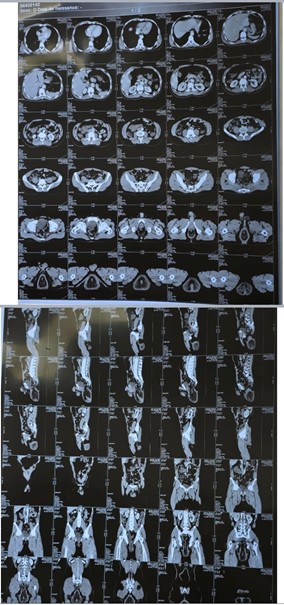

Radiologic Assessment (CT abdominopelvic):

- Full-thickness rectal intussusception through the anal canal (118 mm from the anal verge)

- Associated mesorectal infiltration and small pelvic effusion

- No evidence of bowel obstruction or other visceral abnormalities

Figure 3: Abdominopelvic CT showing complete intussusception of the rectum.

Complicated rectal prolapse, particularly with irreducibility and signs of necrosis, is a surgical emergency. CT scan plays a crucial role in ruling out internal complications and planning surgery. The Altemeier procedure remains an effective and safe technique in this context. Although abdominal approaches (e.g. rectopexy) are common, perineal techniques are favored in acute, ischemic cases to minimize morbidity.

- Radiological assessment is crucial to rule out intra-abdominal complications before surgery.